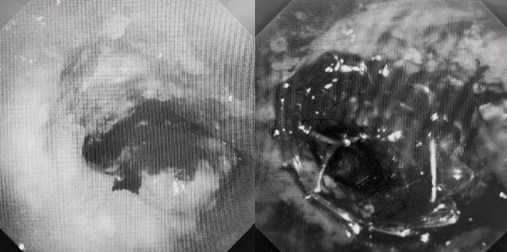

時間就是生命!了解患者病情后,歐陽海峰立刻啟動氣道梗阻緊急救治通道,協(xié)調(diào)院前轉(zhuǎn)運(yùn),急診快速入院流程。凌晨患者入院胸部CT顯示,現(xiàn)存唯一的呼吸通道在右主支氣管處,狹窄處僅約3毫米,患者命懸一線!

患者入院第二天,在麻醉手術(shù)中心全力配合下,歐陽海峰帶領(lǐng)呼吸介入團(tuán)隊(duì),歷時40分鐘快速置入硬質(zhì)支氣管鏡、鏟切腫瘤,并順利植入全覆膜TTS支氣管金屬支架?;颊邭舛贪Y狀即刻緩解,為患者贏得了寶貴的后續(xù)治療機(jī)會。